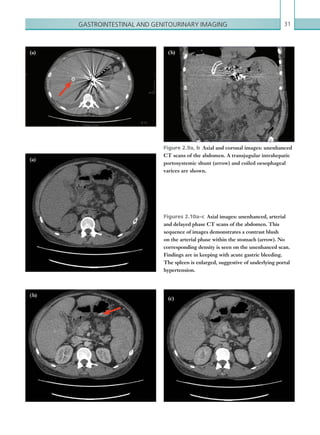

• 80.

Chapter 258 Radiological findings Computedtomography The presence of extraluminal oral contrast in the posterior mediastinum (which can also track into the left-sided pleural cavity) is indicative of oesophageal perforation (Figures 2.48, 2.49). An additional helpful signispneumomediastinum;utilisationoflungwindow settings aids visualisation of this (Figure 2.50). It should be noted that this is a non-specific sign and if seen in isolation, additional causes should be considered (Table 2.15). Concentric or eccentric oesophageal muralthickeningcanalsobeseenincasesofoesophageal perforation, although it is also non-specific and can be seen with oesophagitis or malignancy; the presence of associated para-oesophageal lymphadenopathy is more suggestive of the latter. Para-oesophageal enhancing fluid collections may also be seen. Note: Small oesophageal leaks may be missed on CT, especially in the absence of oral contrast; this should be emphasised in the report. Fluoroscopy Contrast swallow fluoroscopy should be performed with the patient in a semi-supine (20°) position, right Figure 2.48  Axial image: oral and IV contrast enhanced CT scan of the thorax in the arterial phase. Oral contrast is seen collecting in the right pleural space with locules of gas. Left pleural effusion is also noted. Figure 2.49  Axial image: oral contrast CT scan of the thorax. Contrast can be seen within the stomach. Contrast has collected around the oesophagus within the posterior mediastinum (arrow). A left-sided pleural effusion is also present, containing locules of gas. Figure 2.50  Axial image: IV contrast enhanced CT scan of the thorax in the arterial phase. Viewed on lung window settings, gas can be seen surrounding the ­superior mediastinal structures. andleftanterioroblique,rightandleftlateralandprone positions, although this depends on patient tolerance. Ideally, the patient should swallow the oral contrast mediumfromacupondemand.Bolusesoforalcontrast K22247_C002.indd 58 16/05/15 3:07 AM

• 81.

Gastrointestinal and genitourinaryimaging 59 • Blunt chest trauma. • Secondary to chest, neck or retroperitoneal surgery. • Oesophageal perforation. • Tracheobronchial perforation. • Vigorous exercise. • Asthma. • Barotrauma. • Subcutaneous emphysema, pulmonary interstitial emphysema. • Stab wound. • Infection. • Idiopathic. Table 2.15  Causes of pneumostinum. Figure 2.51  PA chest radiograph. Streaky linear ­lucencies are seen within the superior mediastinum and outlining the left heart border. Subcutaneous ­emphysema is also seen in the supraclavicular fossa bilaterally. Reference Tonolini M, Bianco R (2013) Spontaneous esophageal perforation (Boerhaave syndrome): diagnosis with CT-esophagography. J Emerg Trauma Shock 6:58–60. should be followed down the entire oesophagus. Rupture is confirmed in the presence of extravasation of oral contrast or an irregular collection of contrast external to the oesophageal lumen. Additional findings include oesophageal wall irregularity and distortion, which may suggest para-oesophageal collections. Adequate oesophageal luminal distension is vital to identify oesophageal perforation; this requires a good oral contrast load. The study should always be terminated if oral contrast material is aspirated. Plain films Chest plain film findings are all non-specific but can suggest the diagnosis of oesophageal perforation. The most common sign of oesophageal perforation seen on chest plain film imaging is a left-sided pleural effusion and atelectasis/consolidation, reflecting the fact that the most common site of oesophageal perforation is the distal left-sided posterior wall. Pneumomediastinum should always raise suspicion of oesophageal perforation, especially in the presence of associated symptoms. Pneumomediastinum has many appearances on chest plain film imaging, although all rely on the presence of abnormal gas outlining the normal mediastinal structures (Figure 2.51). Note: Pneumomediastinum on plain film imaging has a low sensitivity and specificity for oesophageal rupture and can be seen in many other conditions (Table 2.15). Key points • Oesophageal perforation has a high mortality rate and urgent diagnosis is essential. • Imaging modalities include CT with water soluble oral contrast and fluoroscopy. Small leaks can be missed on both modalities if the oral contrast load is inadequate. Report checklist • Presence or absence of extra-oesophageal oral contrast. • Attempt to localise any potential oesophageal breach. • Document any associated complications (e.g. mediastinal collections and mediastinitis). K22247_C002.indd 59 16/05/15 3:07 AM